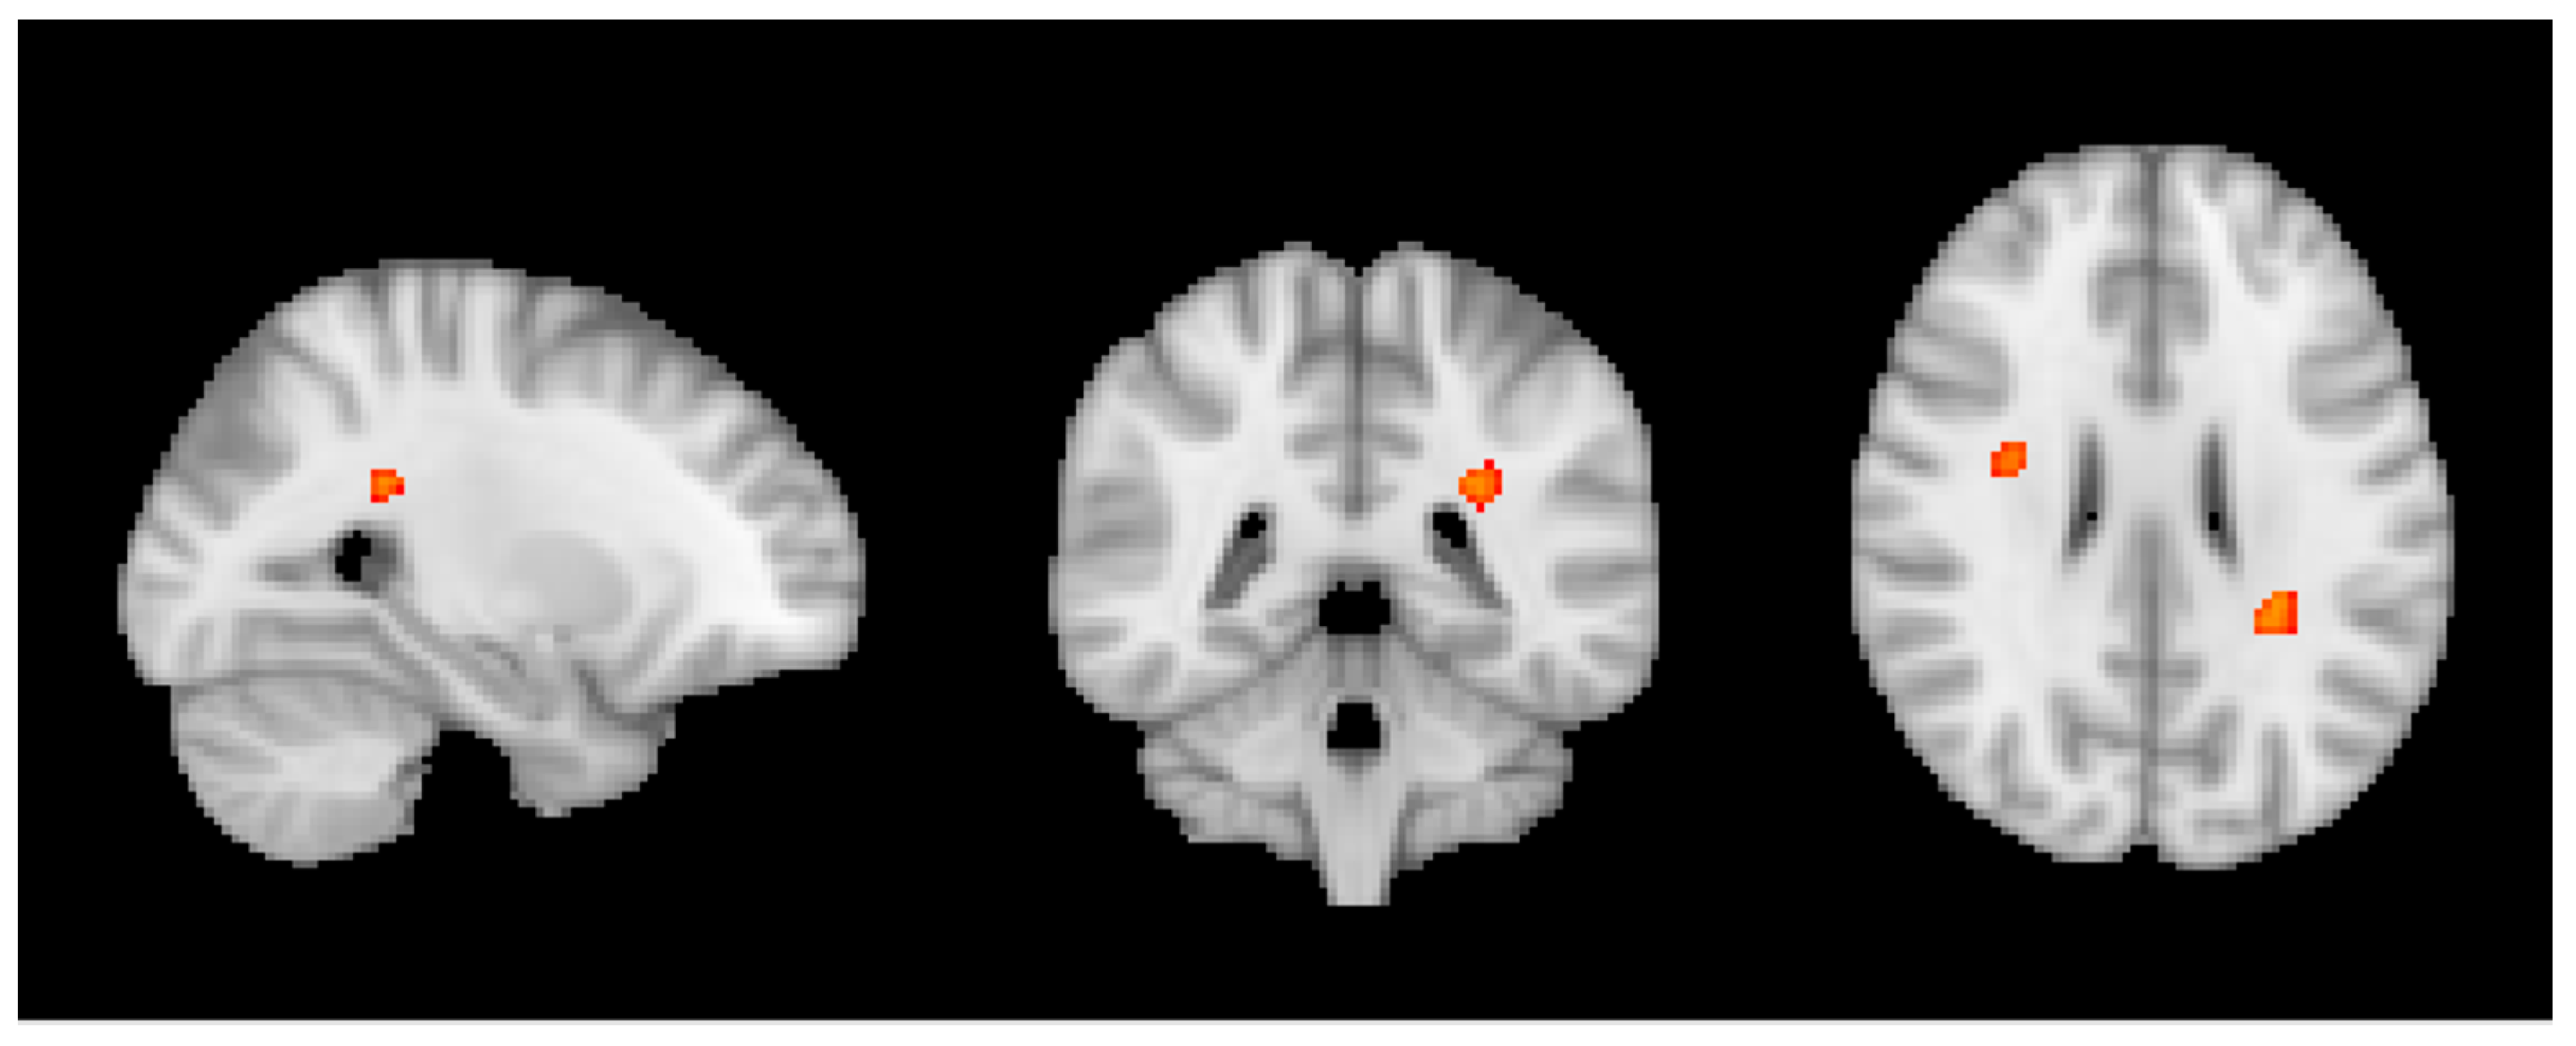

3.3. Group MRI Analysis